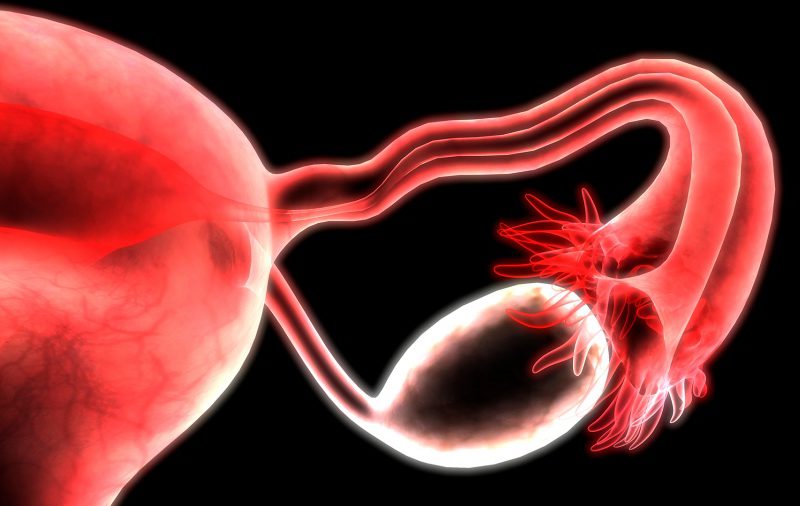

El material de estudio fueron los fluidos foliculares, que se obtienen por aspiración para extraer los óvulos del ovario y usarlos en las técnicas de reproducción asistida.

“En este líquido están los ovocitos (óvulos inmaduros) antes de producirse la ovulación. El material de descarte es el que estudiamos y que está compuesto por una mezcla compleja de hormonas, citoquinas (proteínas del sistema inmune), metabolitos y otras proteínas liberadas por células del ovario y que son importantes para la calidad y el desarrollo de los óvulos”, explicó la doctora en Química Fernanda Parborell, jefa del Laboratorio de Estudios de Fisiopatología Ovárica en el IByME, que depende del Conicet.

Parborell explicó que “para el análisis del líquido folicular se analizan un montón de parámetros entre ellos la vasculatura (irrigación sanguínea) que es lo que hace que el ovario esté bien nutrido”.

La investigadora detalló que “una de las cosas que se observó es que estaba disminuido un factor que es crucial para el crecimiento de los vasos sanguíneos en el ovario que es el factor de crecimiento del endotelio vascular o VEGF, que es una molécula clave en la regulación de la proliferación de las células endoteliales”.

Y continuó: “Esto implica que la vasculatura presente en el ovario estaba alterada, por ende los nutrientes, el oxígeno y las hormonas necesarias para que el ovario tenga una función normal podrían no estar llegando suficientemente para el crecimiento del ovocito”.